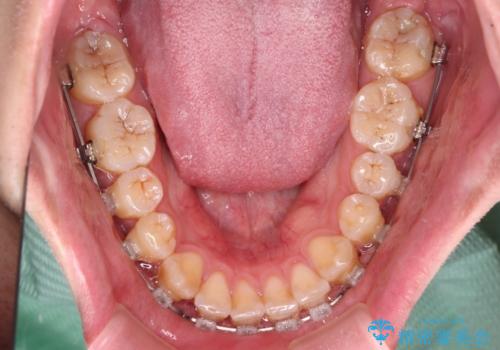

- クリアブラケット

- 1年4ヶ月

上顎側切歯(前から2番目の歯)が内側に転位している歯列は、インビザラインでは排列が困難であることが多いため、期間を短く、より良い仕上がりとするため、ワイヤー装置にて矯正治療を行うこととしました。

治療開始の頃は、食事や歯磨きが慣れず、装置が頻繁に脱落しましたが、2,3ヶ月ほどで慣れ、その後は1年ほどで治療を終えることができました。